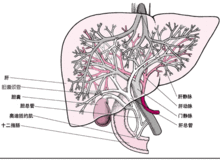

肝臟在人體位置和形態(tài)結(jié)構(gòu):肝臟位于右上腹,隱藏在右側(cè)膈下和肋骨深面,大部分

肝為肋弓所覆蓋,僅在腹上區(qū)、右肋弓間露出并直接接觸腹前壁,肝上面則與膈及腹前壁相接。從體表投影看,肝上界在右鎖骨中線第5肋骨,右腋中線平第6肋骨處;肝下界與肝前緣一致,起自肋弓最低點(diǎn),沿右肋弓下緣左上行,至第8、9肋軟骨結(jié)合處離開(kāi)肋弓,斜向左上方,至前正中線,到左側(cè)至肋弓與第7、8軟骨之結(jié)合處。一般認(rèn)為,成人肝上界位置正常的情況下,如在肋弓下觸及肝臟,則多為病理性肝腫大。幼兒的肝下緣位置較低,露出到右肋下一般均屬正常情況。 肝的位置常隨呼吸改變,通常平靜呼吸時(shí)升降可達(dá)2-3cm,站立及吸氣時(shí)稍下降,仰臥和呼氣時(shí)則稍升,醫(yī)生在給患者肝臟觸診檢查時(shí),常要患者作呼吸配合就是這個(gè)道理。

肝的上面隆凸稱隔面,朝向前上方,與脆彎窿相適應(yīng),能隨呼吸運(yùn)動(dòng)而上下移動(dòng)。隔面借鐮狀韌帶將肝臟分為左右兩部,即左葉和右葉。右葉大而厚;左葉小而薄。肝的下面凹凸不平,稱為臟面,朝向后下方,與腹腔器官相鄰。臟面的中部有H形的兩條縱溝和一條橫溝。左側(cè)縱溝的前部有肝圓韌帶,為胚胎時(shí)期的臍靜脈閉鎖的遺跡;右側(cè)縱溝的前部容納膽囊,后部緊接下腔靜脈。橫溝叫肝門肝固有動(dòng)脈、門靜脈、肝管、淋巴管及神經(jīng)等由此進(jìn)入肝臟。